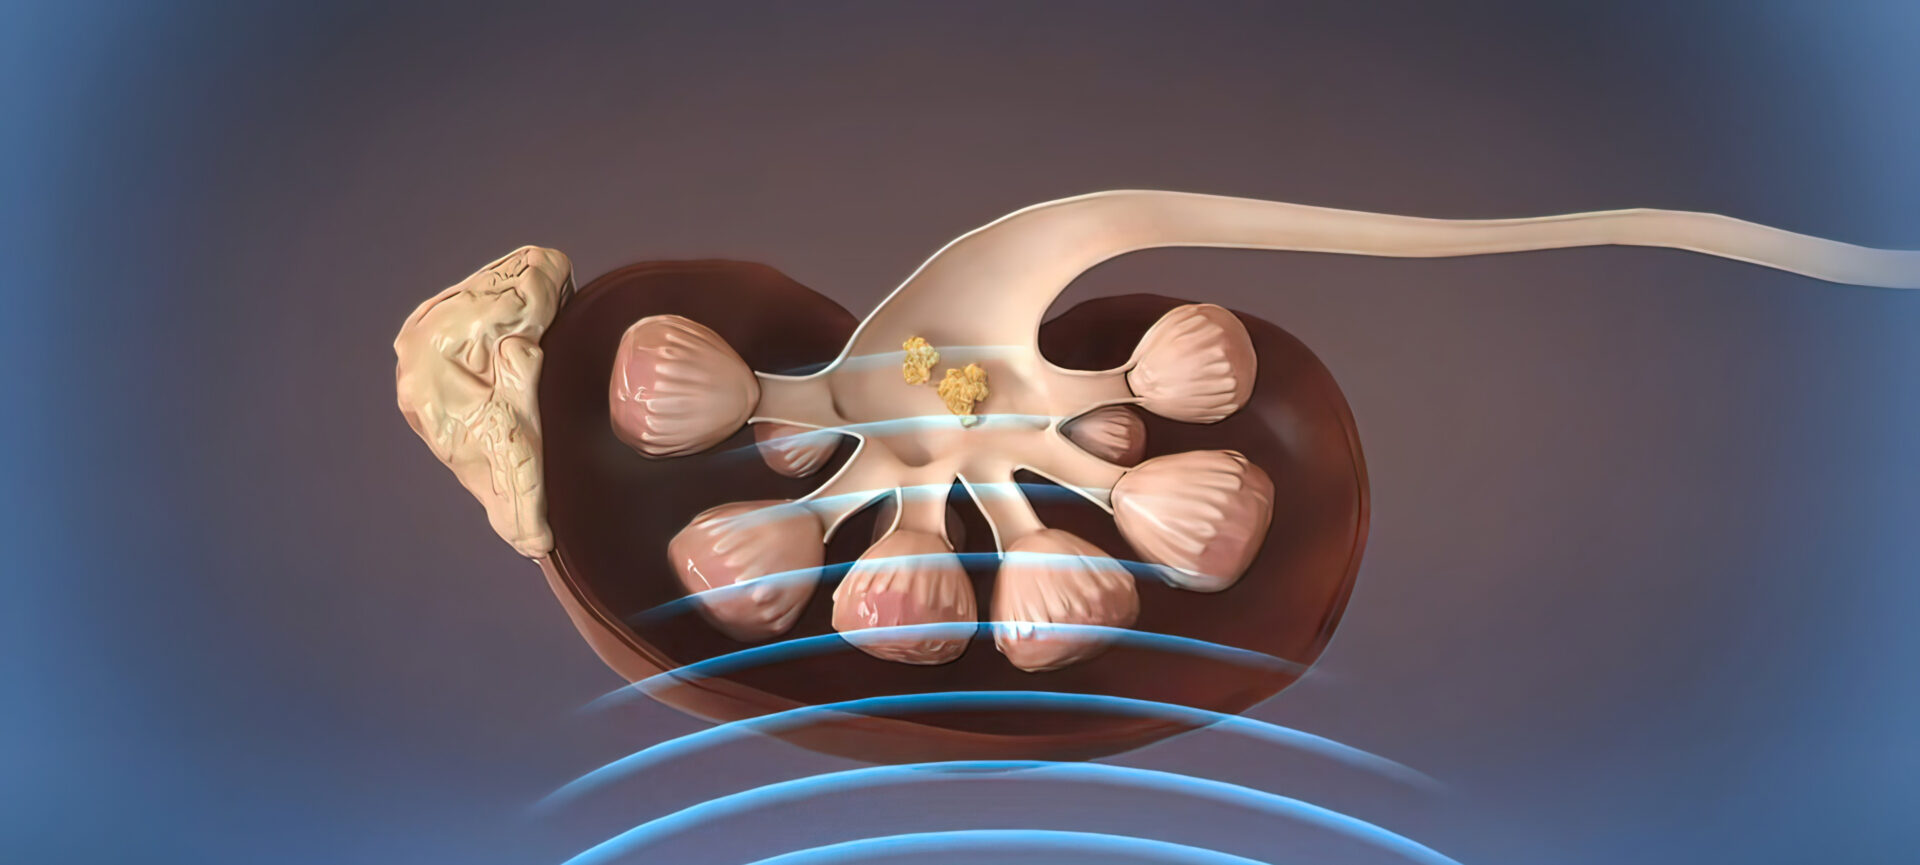

Die Entstehung von Nephrolithen ist komplex und von vielen Faktoren abhängig, die je nach Zusammensetzung des Konkrements variieren und bis heute noch nicht vollumfänglich verstanden sind. Viele Nephrolithen bleiben asymptomatisch und werden per Zufall im Rahmen der bildgebenden Diagnostik entdeckt. Zur Entfernung der Nephrolithen kann unter anderem die Stosswellenlithotrypsie (ESWL) eingesetzt werden, wobei es aber gewisse Komplikationsrisiken zu bedenken gilt.